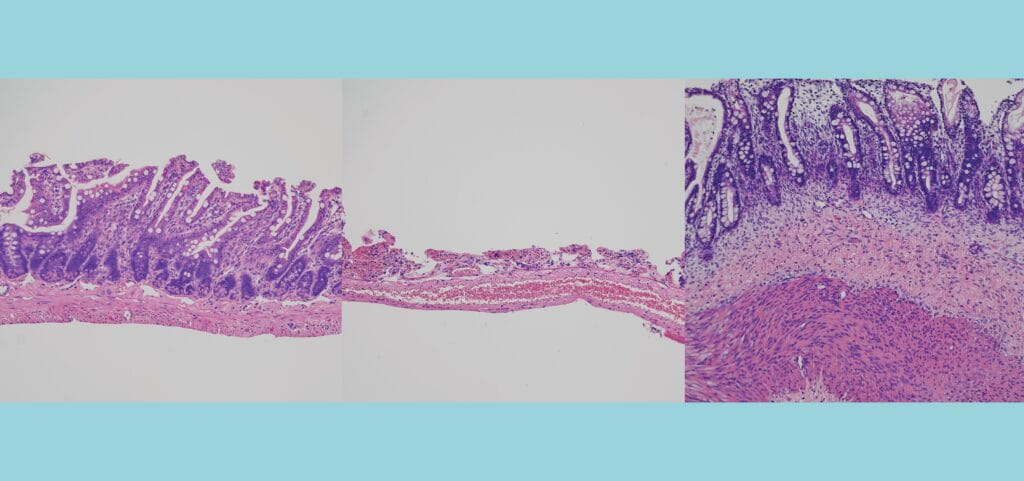

Prior to joining CuSTOM’s leadership team, I led the Intestine-Chip program and managed the multidisciplinary team responsible for developing, translating and commercializing Organs-on-Chips technology. This research has led to major advances in bioengineering of intestinal tissue by combining microchip manufacturing methods and organoid technology and demonstrated the utility of this platform in drug discovery and preclinical development, disease modeling and precision medicine. I was responsible for the development of Intestine-Chip and its successful translation from early-stage research into compelling, validated technology currently being used across academia and industry all around the world. This industry experience enabled me to gain a deep understanding of the processes involved in developing and de-risking technologies from pre-clinical stages to the clinical market.

Combining Human Organoids and Organ-on-a-Chip Technology to Model Intestinal Region-Specific Functionality. Kulkarni, G; Apostolou, A; Ewart, L; Lucchesi, C; Kasendra, M. Journal of Visualized Experiments. 2022; 183.